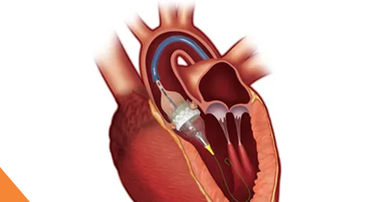

Modern Cardiac Care: The Role of TAVR in Structural Heart Disease Treatment

Nature is just amazing. Look at the amazing things. Just look around, or better yet, look within yourself. Your heart, for example, is a true marvel, working tirelessly, 24/7, never taking even a nap.

Innovative Heart Valve Solutions That Avoid Open-Heart Surgery

For decades, open-heart surgery was the sole method for repairing or replacing a defective heart valve. Although effective, the old method is marked by giant incisions, extended recovery periods, and jeopardy to elderly or high-risk patients.

TAVI Vs. Open-Heart Surgery: Which Is The Right Choice For You?

For heart valve replacement, patients usually have two primary choices: Transcatheter Aortic Valve Implantation (TAVI) and open-heart surgery. Both involve replacing a faulty aortic valve, but they are very different in approach, recovery period, and applicability to various patient populations. Knowing the main differences, advantages, disadvantages, and success rates can assist you in making an informed choice.

Who Is The Ideal Candidate For TAVI? Understanding Eligibility & Benefits

Transcatheter Aortic Valve Implantation (TAVI) has revolutionized the treatment of severe aortic stenosis, especially for patients who are high-risk candidates for traditional open-heart surgery. This minimally invasive procedure offers a lifeline to many, but determining who stands to benefit the most is crucial.